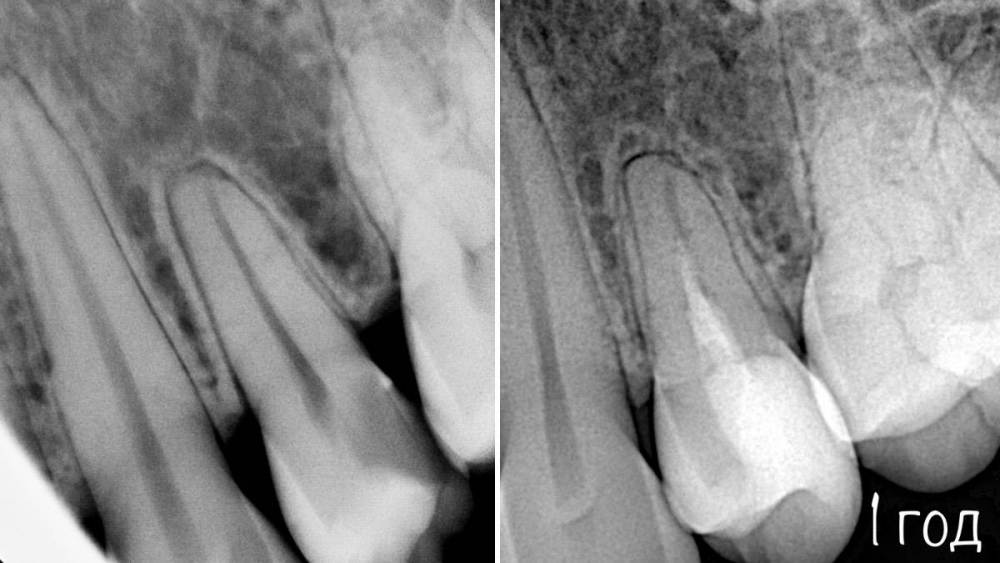

Гарриевич Опубликовано 21 мая, 2022 Поделиться Опубликовано 21 мая, 2022 (изменено) Будущее за регенеративной эндодонтией?) лечение в 2 посещения из-за нехватки времени (новый ассистент, перегруз пациентами, мысли о поднятии стоимости лечения, гипердиагностика?) глубокая пульпотомия, триоксидент, композит. фото подробно выложил это снимок с временной пломбой мало ли что вы подумаете Изменено 21 мая, 2022 пользователем Гарриевич 1 Ссылка на комментарий

Гарриевич Опубликовано 6 апреля, 2023 Автор Поделиться Опубликовано 6 апреля, 2023 3 1 Ссылка на комментарий